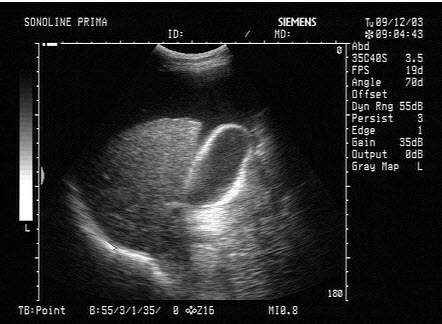

102、单项选择题

胆总管出现图中所示特点,称为()

A.双筒枪征

B.海鸥征

C.鸟嘴征

D.鼠尾征

E.平行管征

103、单项选择题